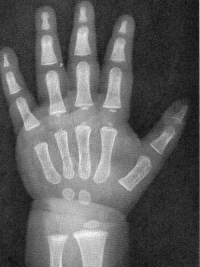

Sexo Feminino

3 meses

6 meses